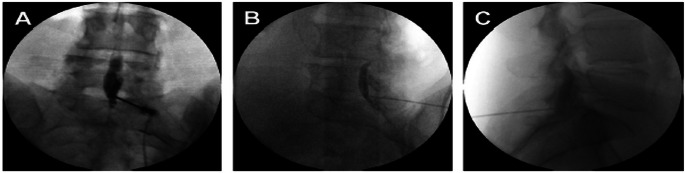

Purpose of review: The purpose of this educational review is to describe the contrast spread patterns that indicate accurate needle placement in the epidural space and spread patterns associated with erroneous needle insertion.

Recent findings: Epidural injections are minimally invasive and commonly used for patients with acute and chronic back pain that does not respond to conservative management. Imaging with contrast is frequently used during this procedure to improve accuracy and reduce adverse events. Contrast spread patterns are an important tool that can help identify where the needle is placed and whether the placement is accurate. Despite this, there may be discrepancies in the interpretation of spread patterns which ultimately reduce the utility of contrast. Inaccurate needle placement may result in intrathecal/subarachnoid, subdural, fascial, or retrodural space of Okada injections. The correct interpretation of contrast spread patterns on imaging is crucial for confirming accurate epidural needle placement. Furthermore, understanding contrast patterns of improper needle placement can prevent adverse events that result from injection outside of the epidural space.